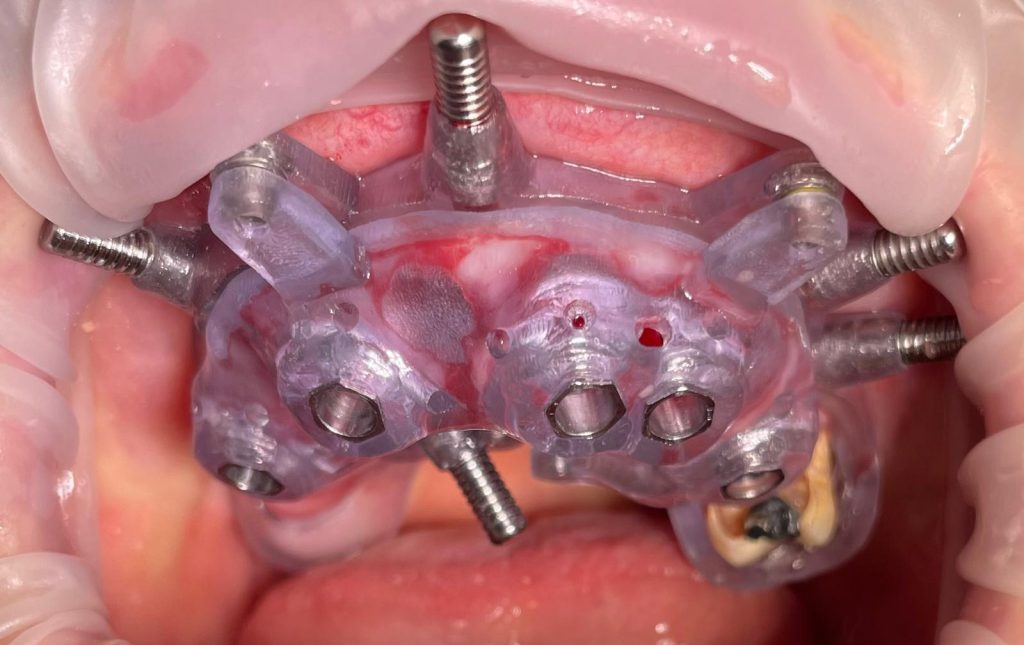

Questa settimana vi presento un caso di riabilitazione immediata dell’arcata superiore eseguita in chirurgia computer guidata con l’utilizzo di dime scomponibili.

L’intervento ha previsto l’estrazione degli elementi dentari, l’inserimento di 5 impianti nell’arcata superiore, il montaggio delle torrette provvisorie e la ribasatura del provvisorio nel cavo orale.